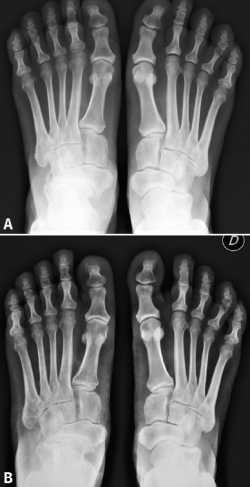

Atendiendo a la clasificación radiológica de Maceira(3), en el preoperatorio encontramos 7 pies (41,2%) en un estadio II, 5 (29,4%) en un estadio III y 5 (29,4%) en un estadio IV. A los 12 meses de la cirugía, se observaron cambios notables en la mayoría de los pacientes, destacando la mejora del aspecto de la artrosis y de la cobertura talonavicular. Tras la cirugía se produjo una regresión en los estadios de Maceira, pasando a tener 6 pies con estadio I (35,3%, ninguno preoperatoriamente), 10 pies con estadio II (58,9%, 7 antes de la cirugía), ningún pie en estadio III (5 antes de la osteotomía) y solo en 1 pie persistió el estadio IV (5,9%, 5 en el preoperatorio) (Figura 3). La mejora de la cobertura talonavicular fue significativa, pasando de una media preoperatoria de − 25,35 (− 17 a − 31) a una postoperatoria de − 15,53 (− 9 a − 26) (Figura 4).

Figura 4. En la proyección radiológica dorsoplantar puede observarse el cambio en la cobertura talonavicular por el desplazamiento del astrágalo antes (A) y un año después de la cirugía (B).